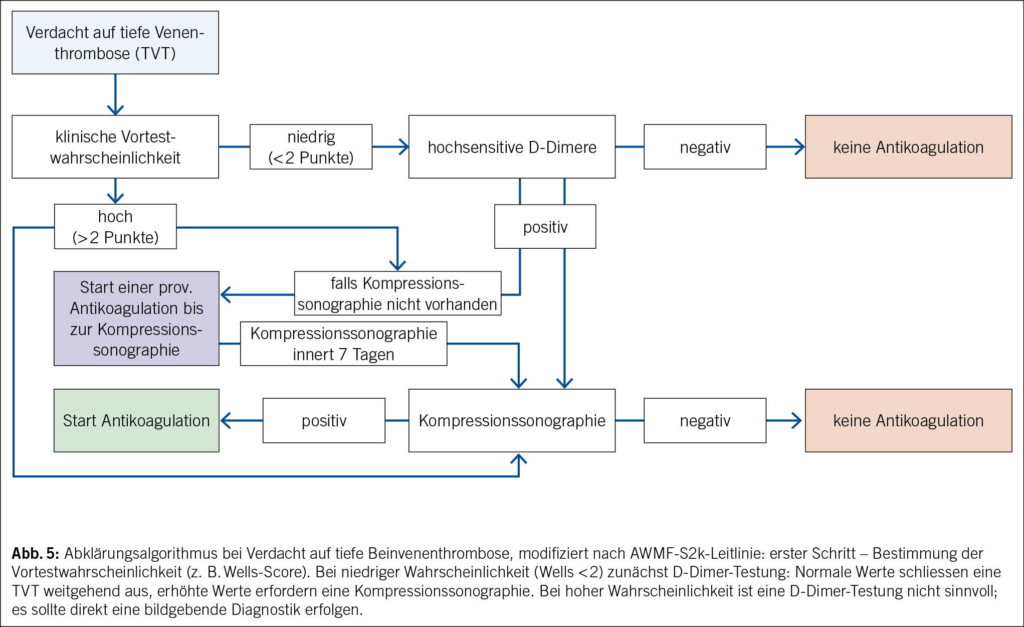

Im Abklärungsalgorithmus der TVT der unteren Extremitäten sind D-Dimere fixer Bestandteil des Abklärungsalgorithmus. Je nach Vortestwahrscheinlichkeit, die mit Scores wie dem Wells-Score berechnet werden kann, werden D-Dimere laboranalytisch bestimmt (bei tiefer/mittlerer Vortestwahrscheinlichkeit). Sind diese erhöht, wird eine Duplexsonographie durchgeführt. Bei hoher Vortestwahrscheinlichkeit wird die D-Dimere-Untersuchung weggelassen und direkt die sonographische Bildgebung durchgeführt (Abb. 5).